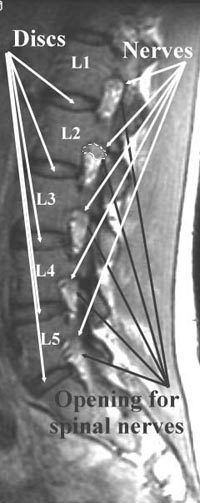

The spinal nerves are in the upper part of the “neural foramina”, or openings or doorways for the spinal nerves, as they go from the spine to the rest of the body.

At L2 (the 2nd lumbar vertebra), the spinal nerve is circled with a white line. The bright material below the nerve is fatty tissue.

The L45 disc (short arrow) is not as bright as the discs near the top of the picture because it has partially dried out. Aging and injury cause a disc to lose water.

The loss of water weakens the disc and decreases its “shock absorber” capabilities. In this case, a fragment of the central part of the disc has slipped backwards and upwards, to narrow the spinal canal

The fine white line surrounds the “neural foramen” or doorway through which the spinal nerves leave the spinal canal to spread out into the body.

This neural foramen can be narrowed by disc herniations, spurs from the margin of the vertebral body, or spurs from the facet joints